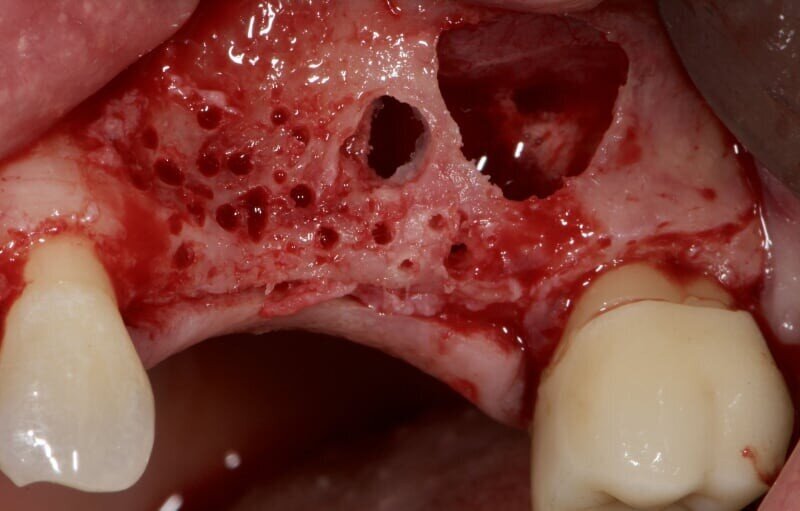

In fase preoperatoria è stato prescritto aerosol (2 volte al giorno per 7 giorni) con beclometasone dipropionato (Clenil 0,8 mg/2 ml) e soluzione ipertonica (Libenar 22g/l) a partire da 7 giorni prima dell’intervento e antibiotico (Amoxicillina 1 g - ogni 12 ore a partire dal giorno precedente l’intervento per 6 giorni). È stato eseguito il rialzo di seno mascellare del secondo quadrante per via laterale abbinato a una contestuale tecnica di GBR/Guided Bone Regeneration (Figg. 4-6). Come sostituto osseo è stato utilizzato lo xenoinnesto bovino Re-Bone® (Ubgen, Padova, Italy) da 1 g con granuli cortico-spongiosi 0,25-1 mm (Figg. 7, 8, 11). Questa metodica è stata abbinata a Shelter ® membrana in pericardio bovino (Ubgen, Padova, Italy) fissata poi con appositi pins ritentivi (Figg. 12, 14, 15). Terminata la tecnica di GBR, sono stati suturati i lembi (Vicryl, 4/0, Johnson & Johnson Int.) (Fig. 16).

Per la fase post-operatoria sono stati prescritti un analgesico da prendere al bisogno (Paracetamolo 500 mg), cortisone (Bentelan 1 mg, 4 compresse il primo giorno e a scalare i giorni successivi fino ad 1 il quarto giorno) e clorexidina 0.2% e sono state fornite istruzioni complete all’igiene orale. Dopo 7 giorni dall’intervento è stato prescritto nuovamente aerosol (beclometasone dipropionato Clenil 0,8 mg/2 ml) e soluzione ipertonica (Libenar 22g/l per 7 giorni). La sutura è stata rimossa dopo 10 giorni. A distanza di 7 mesi dalla procedura rigenerativa è stato attuato un secondo timing chirurgico per posizionare gli impianti nella sede prestabilita. Eseguita l’anestesia locale sono stati inseriti impianti endossei in posizione 24 (3.2 x 10 mm.) e 26 (4.3 x 10 mm) (JD Evolution Plus - JD Dentalcare, Modena, Italy) (Figg. 17, 18) ed eseguita la radiografia di controllo postoperatoria. La rimozione delle suture è avvenuta dopo 10 giorni.